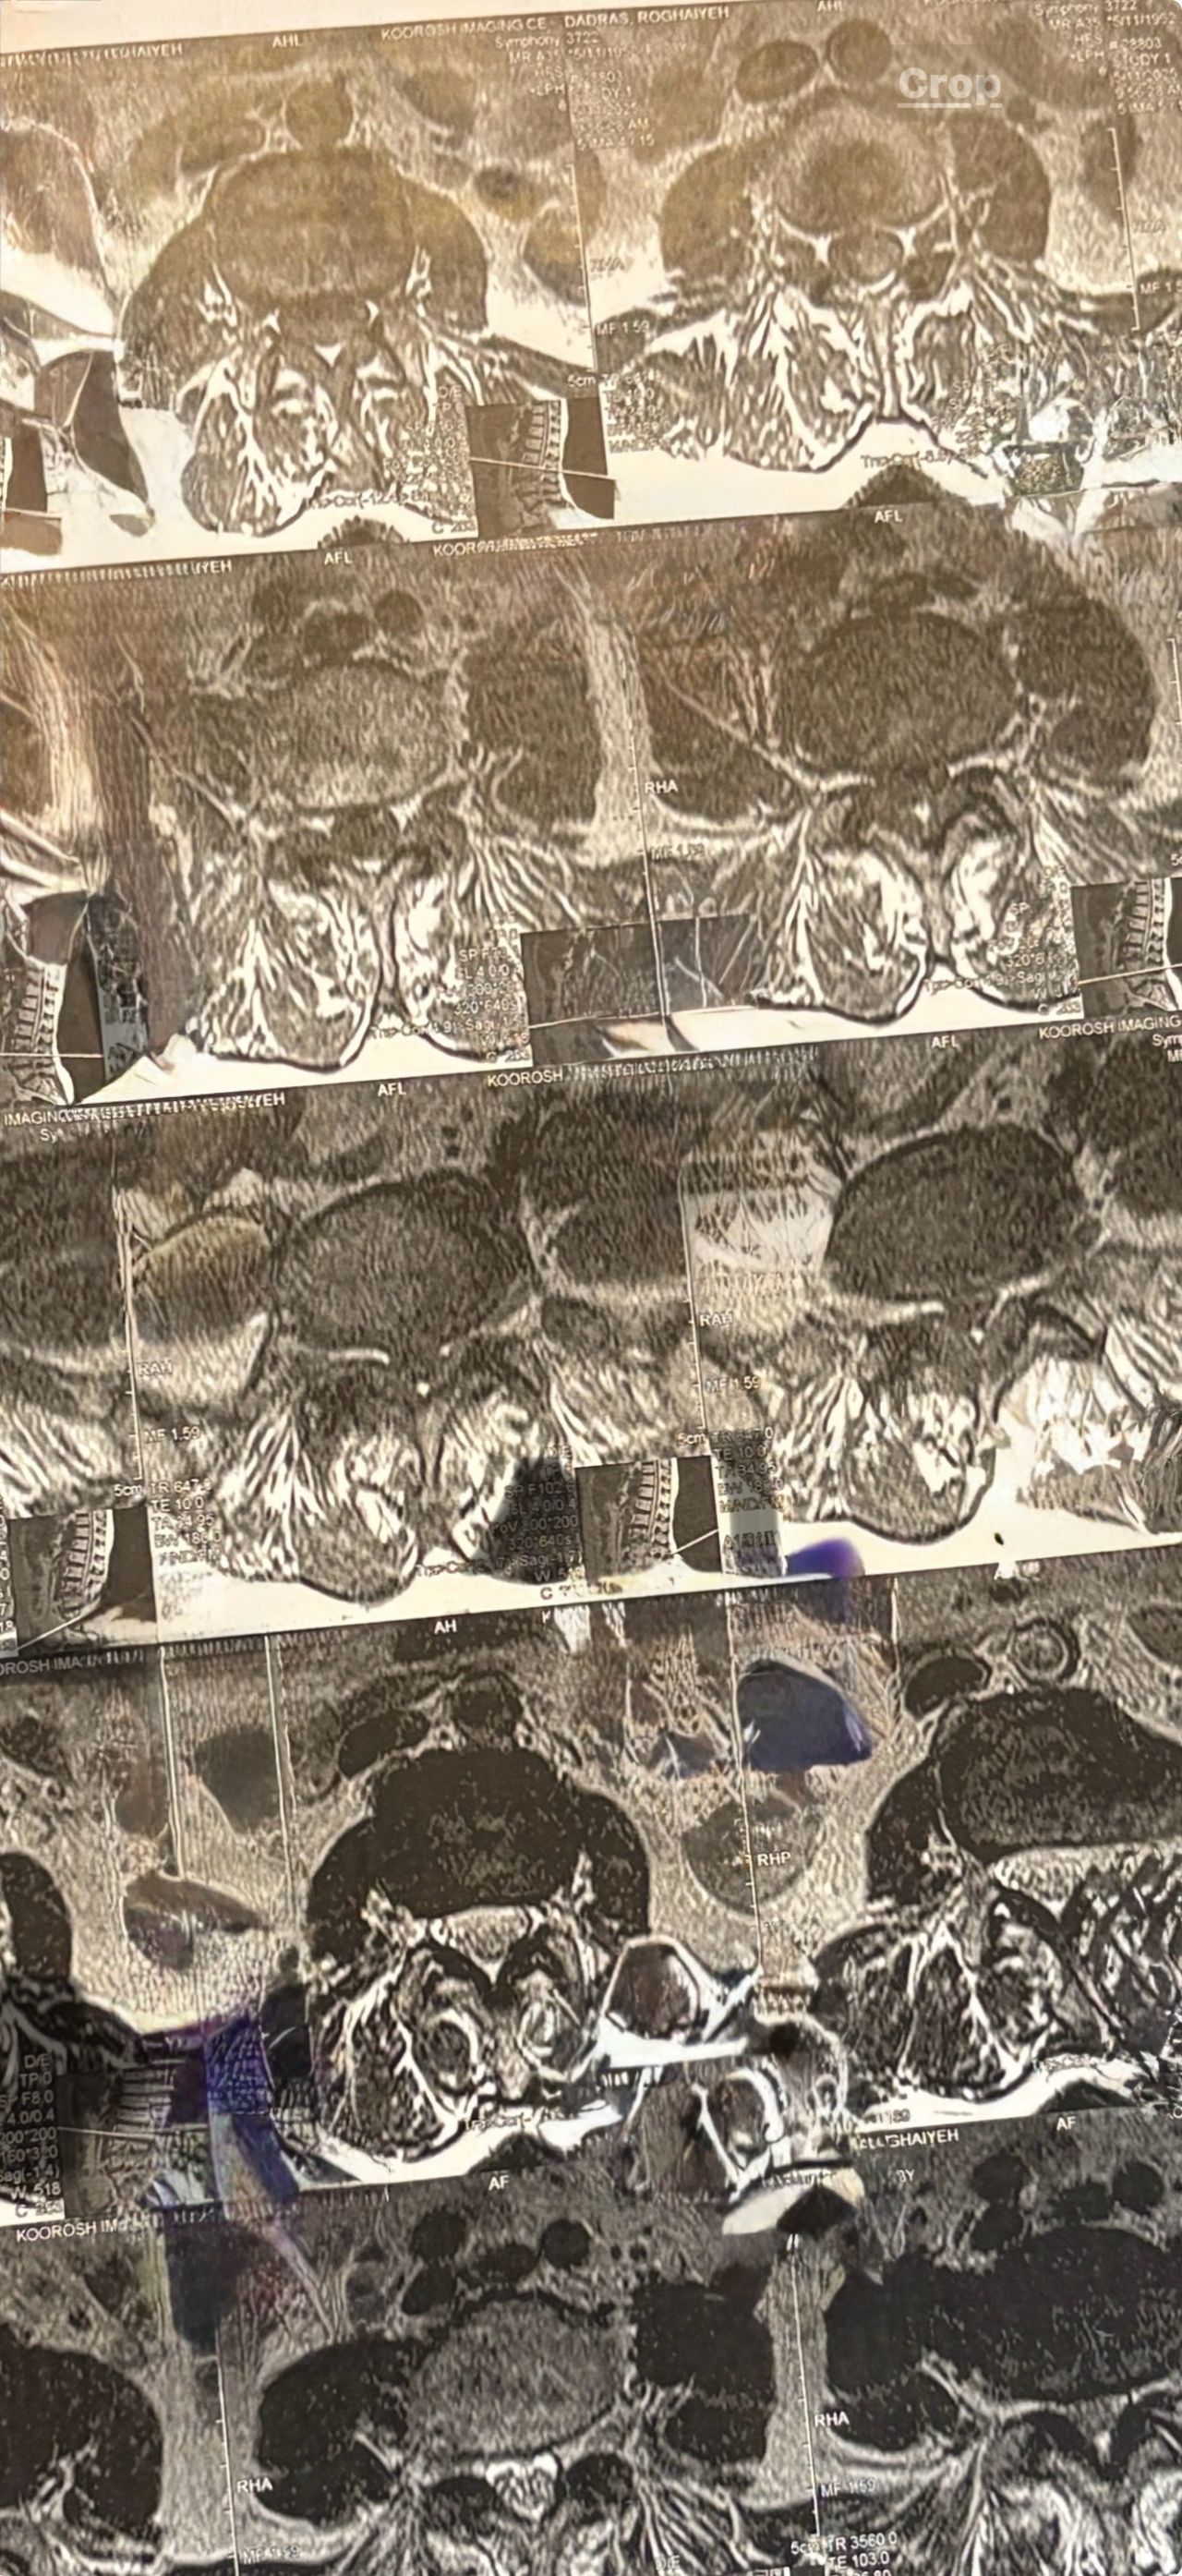

Case 2

After 28 sessions of spinal chiropractic treatments by me using Decompression techniques. without using chiropractic adjustment to the involved disc which is contraindicated in disc extrusions